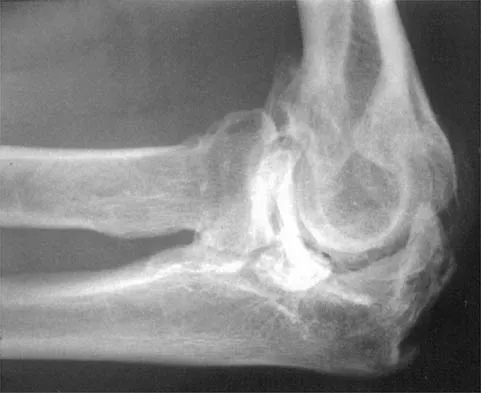

A 52-year-old man who was a former high school pitcher now reports loss of elbow flexion and extension with pain at the extremes of motion. Nonsurgical management has failed to provide relief. Examination reveals movement from 50 degrees to 110 degrees and is painful only at the limits of motion. A radiograph is shown in Figure 12. Treatment should consist of

Explanation

Based on the history, examination, and radiograph, the patient has typical degenerative arthritis of the elbow. This condition is found almost exclusively in men, and there is almost universally a history of repetitive heavy use or overuse of the elbow. Patients report pain at terminal extension and usually have a flexion contracture. Radiographs reveal osteophytes on the coronoid and olecranon and in the coronoid and olecranon fossae. The osteophytes are often associated with loose bodies that sometimes are attached to the soft tissues. Treatment should consist of removal of all loose bodies and impinging osteophytes using open technique or by arthroscopy. The capsular contractures should be released at the same time. Kasser JR (ed): Orthopaedic Knowledge Update 5. Rosemont, IL, American Academy of Orthopaedic Surgeons, 1996, pp 283-294. Morrey BF: Primary degenerative arthritis of the elbow: Treatment by ulnohumeral arthroplasty. J Bone Joint Surg Br 1992;74:409-413. Redden JF, Stanley D: Arthroscopic fenestration of the olecranon fossa in the treatment of osteoarthritis of the elbow. Arthroscopy 1993;9:14-16.